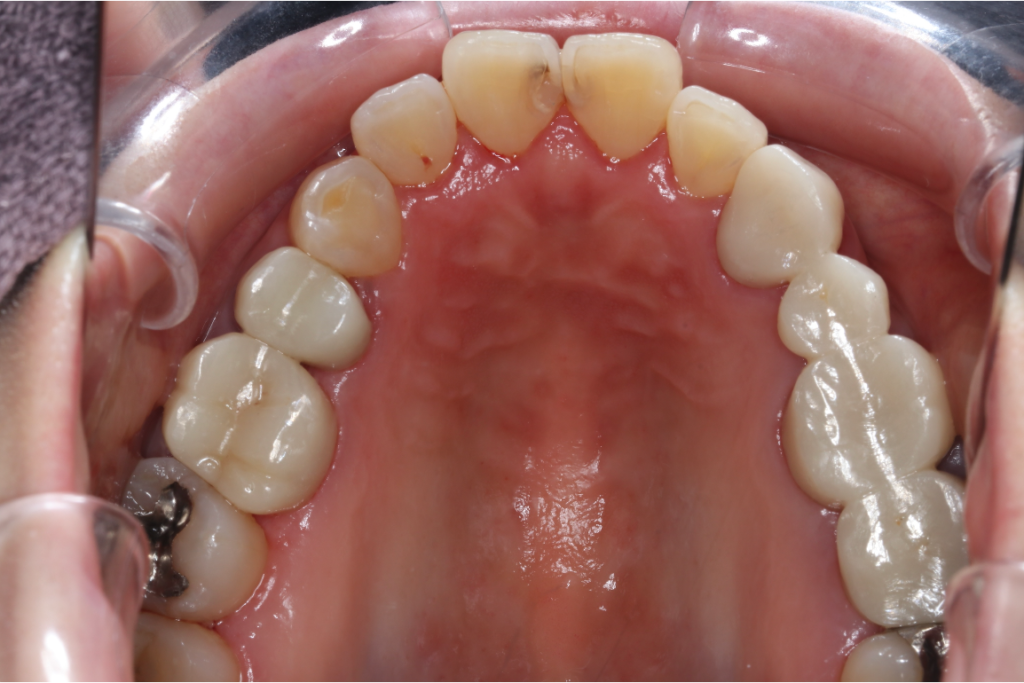

セラミック症例①

年齢40代女性

治療期間1ヶ月

治療内容ジルコニア、セラミックインレー、セラミッククラウン

治療箇所左上1番、2番 左下5番、7番 右上1番、2番、3番、4番、5番 右下5番、6番、7番

治療費用100,000円